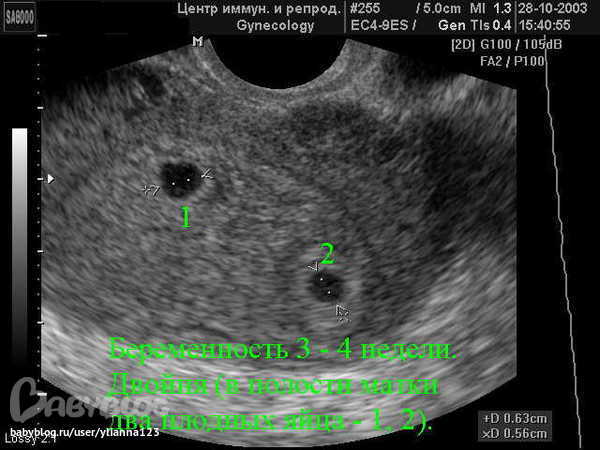

вижу 1 плодное яйцо...вот как двойни выглядят(1 фото 4 недели)(второе 6 недель)

а я почему то вижу...у кружочка что пониже контуры не четкие.и еще раз повторюсь что эта мжет быть гематома

я не спорю про гематому, может как раз она ко второму плодному прилегает и поэтому получается вид как смперматозойдик - головастик с хвостиком

гематома обычно не прелегает она находится между хорионом и стенкой маткино япочемуто не пойму где контуры матки)))у гениколога была?у меня тоже фото какоето странное)))щас покажу с узи на 5ой неделе